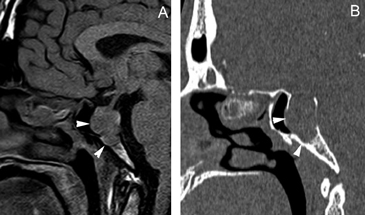

A diferencia de la tomografia computada, que emplea tubos de rayos X, la RM no utiliza radiaciones ionizantes, lo que es una ventaja a considerar en los pacientes pediátricos y en las mujeres embarazadas. La RM tiene una excelente resolución espacial y de tejidos blandos; por ejemplo permite precisar la presencia o ausencia de la neurohipófisis, lo que no es posible con la Tomografia Computada5-7. Con la TAC, con o sin medio de contraste yodado, es posible detectar microadenomas y macroadenomas pituitarios (Figuras 1A y 1B); sin embargo, en los macroadenomas puede ser difícil distinguir las relaciones del tumor con el quiasma óptico, o definir la invasión del seno cavernoso. Además, los artefactos producidos por amalgamas dentales deterioran las imágenes y la dificultad para lograr posiciones cómodas para los pacientes, con el fin de obtener cortes coronales directos, limitan la utilidad de la TAC.

Figura 1A y B. TAC con contraste yodado, corte coronal, muestra un microadenoma lateralizado a izquierda (punta de flecha). Control a los 2 años. TAC con contraste yodado, corte coronal, demuestra aumento de volumen del microadenoma, lo que es infrecuente de observar en clínica (punta de flecha).